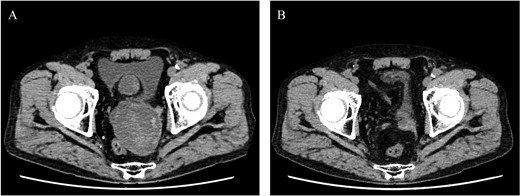

A 68-year-old male was admitted for the expansion of a left IIAA. He had undergone coiling of peripheral branches and stent graft placement in the left common iliac artery (CIA) 10 years prior. Eight years prior, an endoleak was detected between the left CIA and the left IIA. This led to the patient undergoing Y-grafting and disconnection of the CIA and IIAA. Contrast-enhanced computed tomography (CT) revealed a giant IIAA, with a maximum short diameter of 66 mm, and no signs of endoleak (Fig. 1). The aneurysm presented as a cluster of three separate lobes, resembling a dumpling-like structure.

Preoperative computed tomography imaging showing a giant left internal iliac artery aneurysm in a dumpling-like cluster with a maximum short diameter of 66 mm. A—Axial image, B—3D image. LIIAA, left internal iliac artery aneurysm.

Postoperative computed tomography showing a reduction in aneurysm size. A—Preoperative image, B—10-month postoperative image.